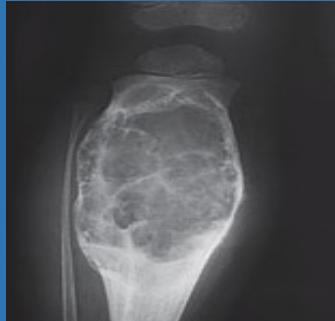

| Open Fracture | A fracture with a breach in the overlying skin and soft tissues, creating communication with the external environment. All open fractures are considered contaminated (even small punctures; aka compound fracture). Causes: Can result from high-energy trauma (RTAs, falls, firearms; signs: degloving, crush syndrome, bone loss, segmental) or low-energy trauma. Contamination risk higher with farm/soil injuries, bites, delayed presentation (>12h), fecal/oral/soil/water exposure. Mechanism: Low/high velocity missiles (cavitation >300 m/s); in-out (cleaner) vs. out-in (dirtier). Gross/Clinical: ![]() | History: Mechanism of injury (energy, time, place, type/impact method), consciousness, wound size/bleeding amount, other injuries (often missed), tetanus status. Assessment: ATLS protocol (ABCDE) first (treat patient, not fracture; exclude shock/brain injury, monitor vitals; viscera exam: ribs=lungs/liver/spleen, pelvis=bladder/urethra). Examine wound (look/feel/move carefully post-splint), check distal neurovascular status, compartment syndrome. Photograph/remove gross contamination; cover with saline dressing. Classification (Gustilo-Anderson): - Type I: <1 cm wound, clean, minimal soft tissue. - Type II: >1 cm wound, moderate soft tissue (no stripping). - Type IIIA: Extensive soft tissue damage, but adequate bone coverage. - Type IIIB: Extensive soft tissue loss with periosteal stripping; bone exposed, requires flap coverage. - Type IIIC: Any open fracture with an arterial injury requiring repair. | Initial (ER): ATLS first. Cover wound with sterile saline-soaked dressing, splint limb, IV fluids (request blood if needed); traction if no distal pulse/deformity. Prophylaxis: Tetanus prophylaxis/serum and broad-spectrum IV antibiotics immediately (culture tissue/blood); clean major contamination. Surgical: Urgent debridement/irrigation within 6-12h (“Dilution is the solution to pollution”; pulse-irrigate 3-6-9L saline; excise non-viable tissue/foreign material, trim skin edges, remove dead muscle/detached bone, preserve N/V). Stabilization: external fixator (preferred severe; replace with cast post-infection); internal if clean/minimal. Wound closure delayed (primary if small/clean; secondary if contaminated/large). Early soft tissue cover. | The diagnosis is typically obvious. Key: Classify severity; identify associated injuries like compartment syndrome, vascular damage, or high-energy signs (e.g., crush). Differentials for contamination: Primary (field debris) vs. secondary (post-fixation if poor debridement). | Complications: Infection (cellulitis, osteomyelitis, chronic with sequestra/drainage, gas gangrene), tetanus; higher with delay/exposure/bites. - embolisms fat, thrombi others.. Case Insight: Unconscious patient (e.g., open tibia post-RTA): ABCDE/cervical collar, distal pulses/traction, admit for debridement; ankle fall: Splint post-ABC, assess neurovascular. |